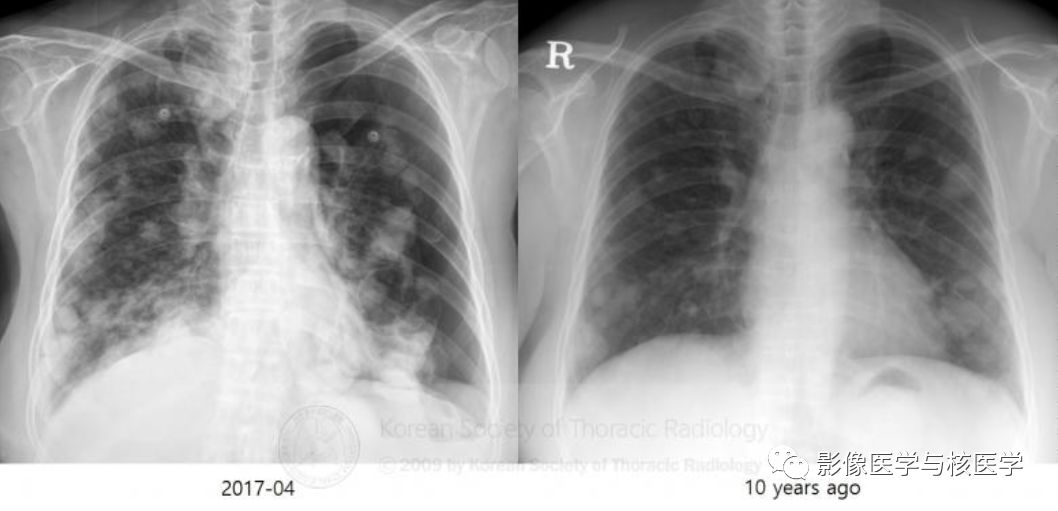

图1 胸片正位(10年前后对比)

Figure 1. Chest PA shows multiple nodules and masses in both lungs with left pneumothorax. There was another previous chest PA from outside hospital taken 10 years ago.

图1.胸片显示两肺多发结节或肿块伴左侧气胸。外院10年前另一胸片。(小编:前后对比病变明显进展)